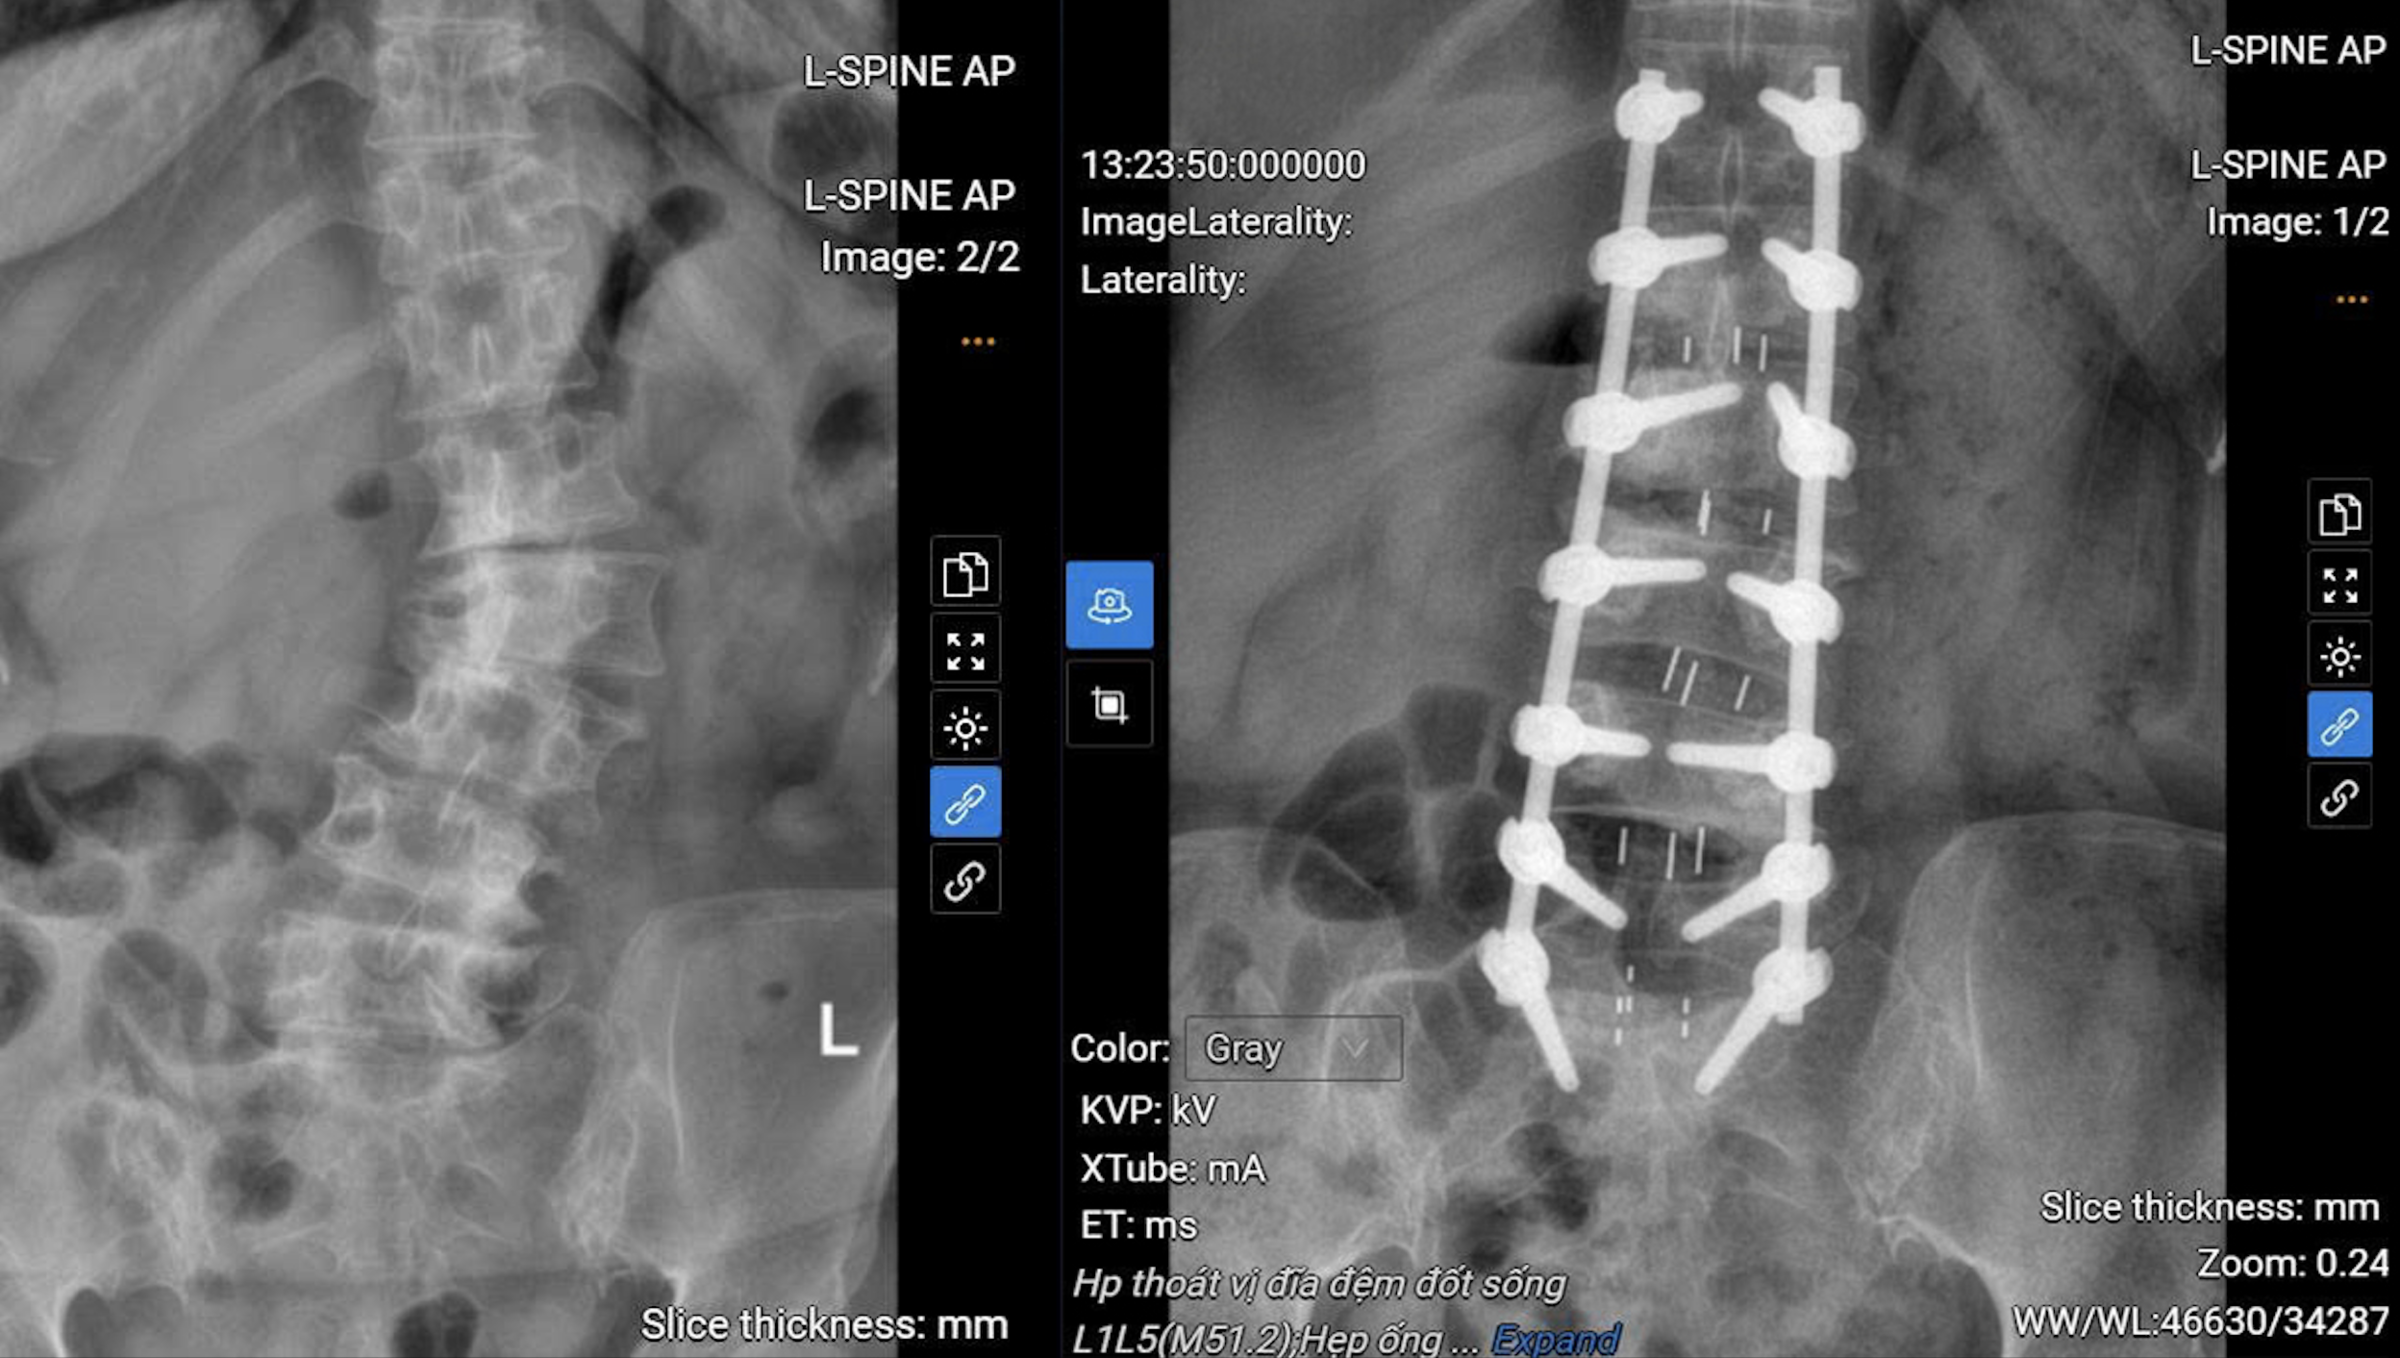

The patient's spine before (left) and after surgery. Photo: Tam Anh General Hospital

Dr. Duan removed the compressing structures and widened the spinal canal, creating space to relieve pressure on the spinal cord and nerve roots. Next, the herniated disc fragments and bone spurs were removed, and a disc replacement was performed to fuse the intervertebral joints, ensuring spinal stability. Finally, the surgeon inserted screws to fix and realign the patient's spine.

A C-arm system assisted the surgeon in accurately positioning the screws, reducing the risk of nerve damage and shortening surgical time. This also minimized blood loss and invasiveness, leading to faster patient recovery. The surgery lasted 5 hours, and 14 screws were used.